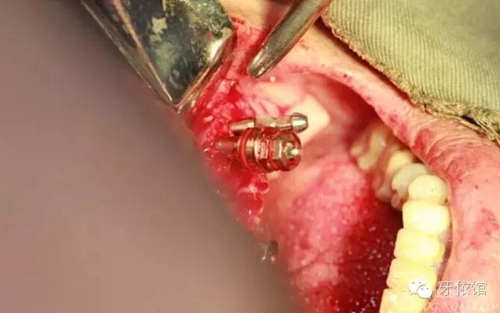

左右3牙位分別植入一顆

切牙壓孔內(nèi)植入植體,扭力50n

其余牙位也分別將植體植入